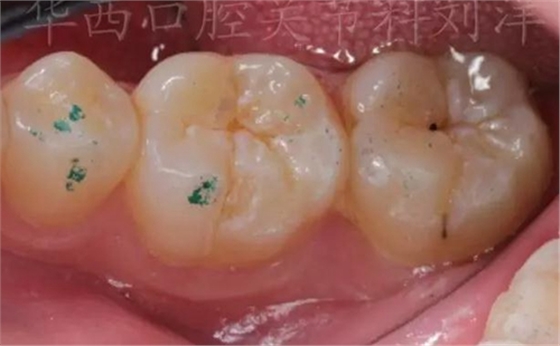

②100微米調均勻后,換40微米細調

▲ 圖3:40µm咬合紙

▲ 圖4:40μm咬合紙的效果